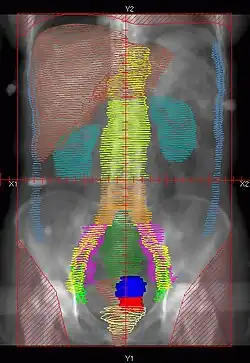

|

Example of a AP whole abdomen/pelvis radiation therapy treatment field used at Tufts/Brown residency program. Actual patient contours should guide field design.

|